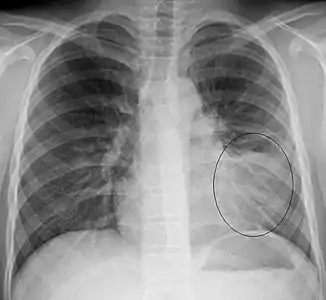

AP CXR showing left lower lobe pneumonia associated with a small left sided pleural effusion

AP CXR showing pneumonia of the lingula of the left lung

Right upper lobe pneumonia as marked by the circle.

Left upper lobe pneumonia with a small pleural effusion.